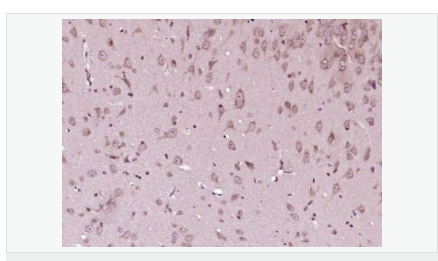

| 产品应用 | WB=1:500-2000 ELISA=1:5000-10000 IHC-P=1:100-500 IHC-F=1:100-500 Flow-Cyt=1μg/Test ICC=1:100-500 IF=1:100-500 (石蜡切片需做抗原修复) not yet tested in other applications. optimal dilutions/concentrations should be determined by the end user. |

| 产品介绍 | This gene encodes a cyclin-dependent kinase inhibitor, which shares a limited similarity with CDK inhibitor CDKN1A/p21. The encoded protein binds to and prevents the activation of cyclin E-CDK2 or cyclin D-CDK4 complexes, and thus controls the cell cycle progression at G1. The degradation of this protein, which is triggered by its CDK dependent phosphorylation and subsequent ubiquitination by SCF complexes, is required for the cellular transition from quiescence to the proliferative state. [provided by RefSeq, Jul 2008] Function: Important regulator of cell cycle progression. Involved in G1 arrest. Potent inhibitor of cyclin E- and cyclin A-CDK2 complexes. Forms a complex with cyclin type D-CDK4 complexes and is involved in the assembly, stability, and modulation of CCND1-CDK4 complex activation. Acts either as an inhibitor or an activator of cyclin type D-CDK4 complexes depending on its phosphorylation state and/or stoichometry. Subunit: Forms a ternary compex with CCNE1/CDK2/CDKN1B. Subcellular Location: Nucleus. Cytoplasm. Endosome. Note=Nuclear and cytoplasmic in quiescent cells. AKT-or RSK-mediated phosphorylation on Thr-198, binds 14-3-3, translocates to the cytoplasm and promotes cell cycle progression. Mitogen-activated UHMK1 phosphorylation on Ser-10 also results in translocation to the cytoplasm and cell cycle progression. Phosphorylation on Ser-10 facilitates nuclear export. Translocates to the nucleus on phosphorylation of Tyr-88 and Tyr-89. Colocalizes at the endosome with SNX6; this leads to lysosomal degradation. Tissue Specificity: Expressed in all tissues tested. Highest levels in skeletal muscle, lowest in liver and kidney. Post-translational modifications: Phosphorylated; phosphorylation occurs on serine, threonine and tyrosine residues. Phosphorylation on Ser-10 is the major site of phosphorylation in resting cells, takes place at the G(0)-G(1) phase and leads to protein stability. Phosphorylation on other sites is greatly enhanced by mitogens, growth factors, cMYC and in certain cancer cell lines. The phosphorylated form found in the cytoplasm is inactivate. Phosphorylation on Thr-198 is required for interaction with 14-3-3 proteins. Phosphorylation on Thr-187, by CDK2 leads to protein ubiquitination and proteasomal degradation. Tyrosine phosphorylation promotes this process. Phosphorylation by PKB/AKT1 can be suppressed by LY294002, an inhibitor of the catalytic subunit of PI3K. Phosphorylation on Tyr-88 and Tyr-89 has no effect on binding CDK2, but is required for binding CDK4. Dephosphorylated on tyrosine residues by G-CSF. Ubiquitinated; in the cytoplasm by the KPC complex (composed of RNF123/KPC1 and UBAC1/KPC2) and, in the nucleus, by SCF(SKP2). The latter requires prior phosphorylation on Thr-187. Ubiquitinated; by a TRIM21-containing SCF(SKP2)-like complex; leads to its degradation. DISEASE: Defects in CDKN1B are the cause of multiple endocrine neoplasia type 4 (MEN4) [MIM:610755]. Multiple endocrine neoplasia (MEN) syndromes are inherited cancer syndromes of the thyroid. MEN4 is a MEN-like syndrome with a phenotypic overlap of both MEN1 and MEN2. Similarity: Belongs to the CDI family. SWISS: P46527 Gene ID: 1027 Database links: Entrez Gene: 1027 Human Entrez Gene: 12576 Mouse Omim: 600778 Human SwissProt: P46527 Human SwissProt: P46414 Mouse Unigene: 238990 Human Unigene: 2958 Mouse Important Note: This product as supplied is intended for research use only, not for use in human, therapeutic or diagnostic applications. P27蛋白是一种新发现的周期素依赖激酶抑制剂,属于细胞周期的负性调控因子。P27基因及其产物的异常表达可能与某些肿瘤的发生、发展有着密切的关系。P27蛋白对细胞周期的调控及在肿瘤中发挥着很重要的作用。 |